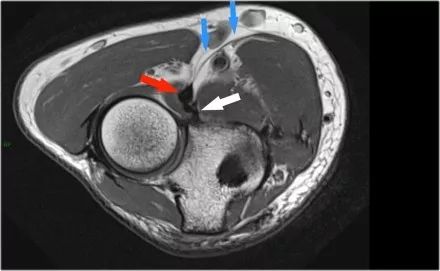

冠状图像上有一个美丽的UCL前束,但注意到关节内侧部分有骨赘形成(红色箭头)。当我们按照顺序向下看,可以看到存在一小部分低信号强度(黄色箭头),这是UCL的一部分撕裂。

这是在X线片可以更好地观察(黄箭头 )。

当我们看轴向扫描时,我们可以欣赏巨大的骨赘形成。请注意,尺骨神经(蓝色箭头)紧邻这些骨赘,这些可能指示尺神经出现病变。